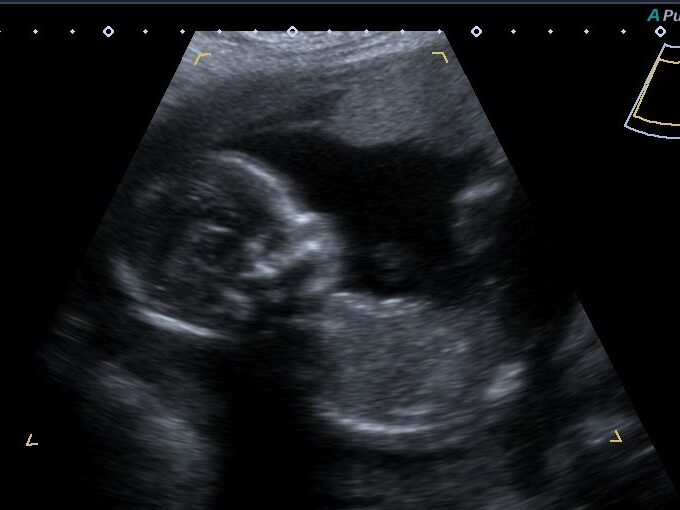

Traditionally, prenatal visits include ultrasounds, blood and urine tests, or other exams that allow the doctor to evaluate your condition and that of the fetus so that both can face pregnancy and childbirth in the best possible conditions.

- Basic and structural ultrasound

- Fetal growth evaluation

- Follow-up ultrasound for pathologies